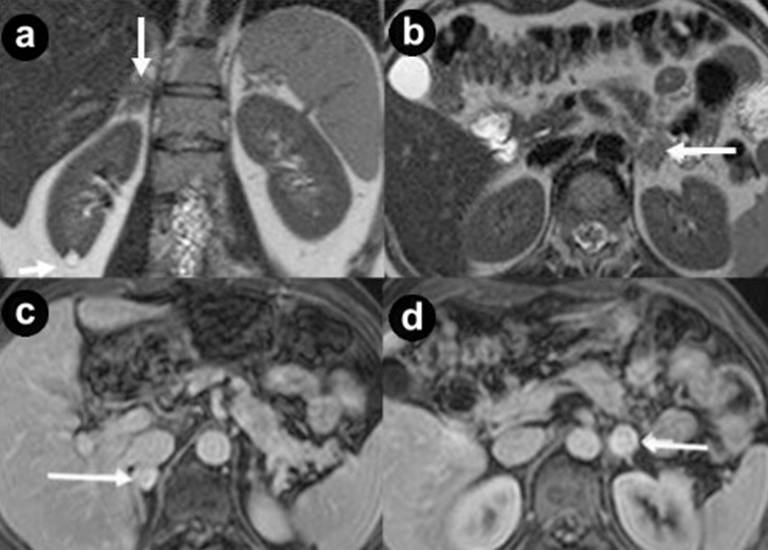

Figure 6. Pancreatic diffuse cystic non functioning neuroendocrine tumor. A 43-year-old woman affected by VHL disease. Axial T2-weighted MR images (a.) and 3D volumetric gradient-echo T1-weighted fat suppressed images after intravenous contrast medium administration during arterial pancreatic (b.), portal venous (c.) and delayed (d.) phases of contrastographic dynamic study. Pancreatic gland is enlarged and parenchyma is thickened, completely replaced by multiple, lobulated fluid cysts, the largest in pancreatic head and tail (arrows), hyperintense in T2-weighted MR images, with thickened walls and irregular septa. Multiple small parenchymal nodules (small arrows), hyperintense on T2-weighted MR images but with lower signal intensity compared to fluid lesions, are visible in pancreatic body-tail and head. After intravenous contrast medium administration during arterial pancreatic (b.), portal venous (c.) and delayed phases (d.) walls and septa of cystic lesions show enhancement. Also multiple, small, solid parenchymal nodules enhance during pancreatic phase of dynamic MR study (short arrows). A large fluid cystic lesion in pancreatic head causes stenosis of main pancreatic duct and upstream duct dilatation (arrowhead). Total pancreatectomy and retroperitoneal lymphadenectomy was performed. Histological specimen showed the presence of pancreatic diffuse non functioning neuroendocrine carcinoma with malignant cystic and solid lesions. Retroperitoneal adenopathy metastasis were present. |

Figure 7. Renal cysts and cystic renal cell carcinoma. A 43-year-old man with VHL disease. Coronal (a. b.) and axial (c.) T2-weighted MR images; axial (d.) and coronal (e. f.) 3D volumetric gradient-echo T1-weighted fat suppressed images after intravenous contrast medium administration during arterial (d. e.) and venous (f.) phases of contrastographic dynamic study. Multiple and bilateral simple, fluid renal cysts, with high signal intensity on the T2-weighted images (a. b. c.) and hypointense without enhancement after intravenous contrast medium administration during arterial (d. e.) and venous (f.) phases. In the lower pole of the left kidney a complex cystic mass (arrows) is present, with heterogeneous hyperintensity on the T2-weighted images, septa and solid areas enhanced after intravenous contrast medium administration during arterial (d. e.) and venous (f.) phases. Surgical enucleation of left renal lesion was performed. Histological specimen showed the presence of a cystic renal cell carcinoma.

Figure 8. Adrenal pheochromocytomas. A 38-year-old man with VHL disease. Coronal (a.) and axial (b.) T2-weighted MR images; axial (c. d.) 3D volumetric gradient-echo T1-weighted fat suppressed images after intravenous contrast medium administration during portal venous phase of contrastographic dynamic study. In both adrenal glands, small, round solid masses (arrows), with maximum diameter of 20 mm and intermediate signal intensity in T2-weighted MR images (a. b.) are present. The nodules show intense and homogeneous enhancement after intravenous contrast medium administration during dynamic study (c. d.). Small cyst at lower pole of right kidney (a. short arrow). Bilateral open adrenalectomy was performed. Histological specimen showed the presence of adrenal bilateral pheochromocytomas. |

Figure 9. Papillary cystadenoma of the epididymis. A 38-year-old man with VHL disease (the same case of Figure 8). Coronal 3D volumetric gradient-echo T1-weighted fat suppressed images after intravenous contrast medium administration during portal venous phase of contrastographic dynamic study. Bilateral complex cystic mass of epididymis with extratesticular site, fluid components, irregular septa inside the lesion and solid mural nodules which show enhancement after intravenous contrast medium administration during arterial phase (asterisks). Testicular resection was performed. Histological specimen showed the presence of bilateral papillary cystadenoma of the epididymis. |

Thirty-four pancreatic lesions were found in the 23 patients. In qualitative analysis, the MR imaging findings were: 6 (26.1%) unilocular fluid cystic lesions (Figure 1abc): 3 (13.0%) in pancreatic head, 3 (13.0%) in pancreatic body-tail; 11 (47.8%) serous micro- or micro/macro-cystic cystadenomas (Figures 1def, 4, and 5): 1 (4.3%) in pancreatic head, 2 (8.7%) in pancreatic body-tail (Figure 1), 8 (34.8%) diffuse (Figures 4 and 5); 8 (34.8%) neuroendocrine solid tumors: all of them non-functioning NET and hypervascular during arterial pancreatic phase of contrastographic dynamic study (Figures 2, 3, 4, and 5), 4 (17.4%) at pancreatic head (Figures 2ab; 3ace, and 4), 4 (17.4%) at pancreatic body-tail (Figures 2cd and 5); 1 (4.3%) cystic non-functioning NET, diffuse in all pancreatic gland (Figure 6); in 4 (17.4%) cases association of non-functioning NET and pancreatic cystic lesions (3 cases of association of non-functioning NET and serous cystadenoma (13.0%); 1 case of association of non-functioning NET and pancreatic simple cystic lesion (4.3%)) were present (Figures 4 and 5). Vascular invasion was not detected in any patients.

The 42 renal MR imaging findings present in qualitative analysis were: 18 (78.3%) renal cysts: 16 (69.6%) bilateral and multiple and 2 (8.7%) single (Figures 2d, 4ab, 5adef, and 7abcdef); 13 (56.5%) complex renal cysts: including 10 (43.5%) benign complex renal cysts (Figures 1a and 2b) and 3 (13.0%) malignant or cystic renal carcinoma (Figures 4ef and 7bcdef); 11 (47.8%) solid renal carcinomas hypervascular during arterial phase of contrastographic study with wash-out during portal venous phase: 5 (21.7%) multiple and bilateral and 6 (26.1%) single. Only 1 of these 11 lesions at pathological specimen resulted benign or adenoma.

The adrenal MR imaging findings were: 3 (13.0%) solid hypervascular tumors: 2 of these (66.7%) bilateral and 1 (33.3%) monolateral (Figure 8abcd).

The scrotum MR imaging findings were: 1 (4.3%) fluid cystic lesion or cystadenoma (Figure 9) and none solid lesion.

MR findings [3, 9, 15, 16, 38] of renal carcinoma in patients with VHL syndrome are low signal intensity at T1-weighted images and high signal intensity at T2-weighted images, hypervascular with enhancement during arterial phase of contrastographic dynamic study, hypointense with wash-out in venous phase solid mass. The hypervascularity of renal lesions is probably related to increased levels of vascular endothelial growth factors, and other angiogenic factors produced by these hereditary tumors [41, 42].

Frequently, renal carcinoma in patients with VHL syndrome may present as complex cystic masses [15, 19] with fluid component, mural nodules, thick walls and septa showing enhancement on T1-weighted images after intravenous gadolinium contrast medium administration (Figures 4ef and 7bcdef). Malignant complex cysts may show a low-signal intensity walls on T2-weighted images (pseudocapsule).

At MR imaging the lesions are usually iso- or hypointense on T1-weighted images compared to the liver, they do not lose signal intensity in T1-weighted images in opposition of phase, and they are hyperintense on T2-weighted images (Figure 8ac), with marked gadolinium enhancement [3, 4, 9, 15, 16, 50, 51, 52] during arterial phase of contrastographic dynamic study (Figure 8bd).